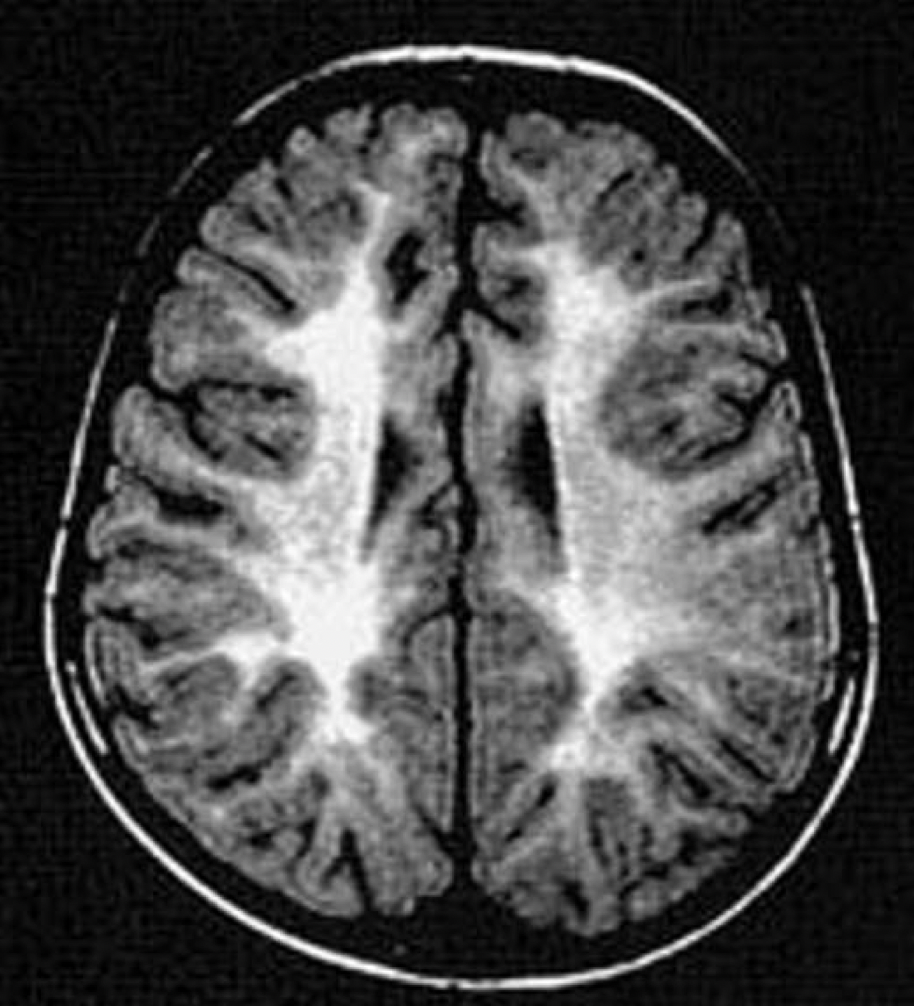

Imagem 3

A intoxicação por monóxido de carbono (CO)